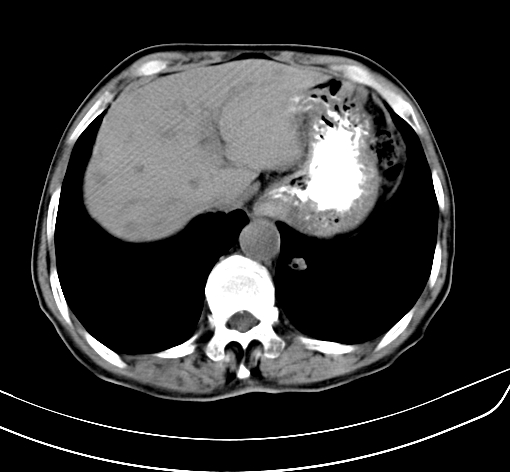

病人 男 70 咳嗽 胃部不适 2月余

胆囊壁增厚,与临近肝实质边界不清,临近肝实质内可见大片边界不清之低密度区,肝门区密度亦有减低,部分结构不清,尾叶前方可见块状影,肝右叶可见多枚边界不清之圆形低密度区,肝内胆管扩张征象,结合病史考虑1胆囊癌肝内转移,肝门区淋巴结转移,门脉癌栓待排2肝内胆管扩张3建议增强扫描

肝脏多发大小不等低密度灶,边界不清,肝门区结构不清,肝内胆管轻度扩张,胆囊密度不均匀,内见软组织样密度影,与相临肝脏边界不清.考虑:1、胆囊ca侵犯肝脏并肝内多发转移,肺上也有结节影,转移?建议强化扫描.2、胃充盈不好,如怀疑有病变最好建议做相关检查.

胆囊壁增厚,周围模糊不清,肝内多发低密度影,胃充盈欠佳,胃壁增厚,外形尚规整,考虑胆囊炎、胆囊癌肝内转移?建议胃肠道进一步检查或增强扫描。